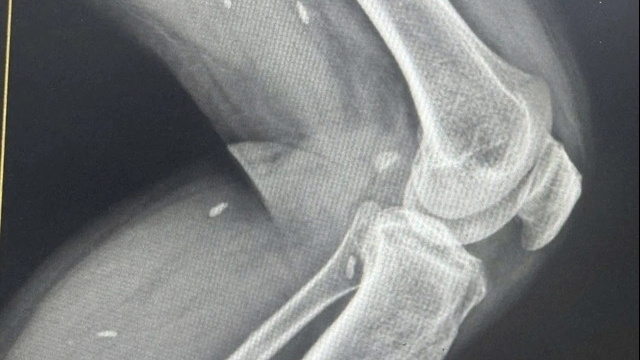

Sau khi ổn định được mạch, huyết áp, đóng bụng vừa xong, bác sĩ gây mê hồi sức phối hợp với các bác sĩ Tim mạch can thiệp - Bệnh viện Chợ Rẫy tiến hành siêu âm tim, phát hiện bệnh nhân có tình trạng dãn buồng tim bên phải (thất phải). Đồng thời thấy được huyết khối ở thất phải của tim và ở tĩnh mạch cảnh bên phải. Đây là một trường hợp điển hình của thuyên tắc phổi do huyết khối.